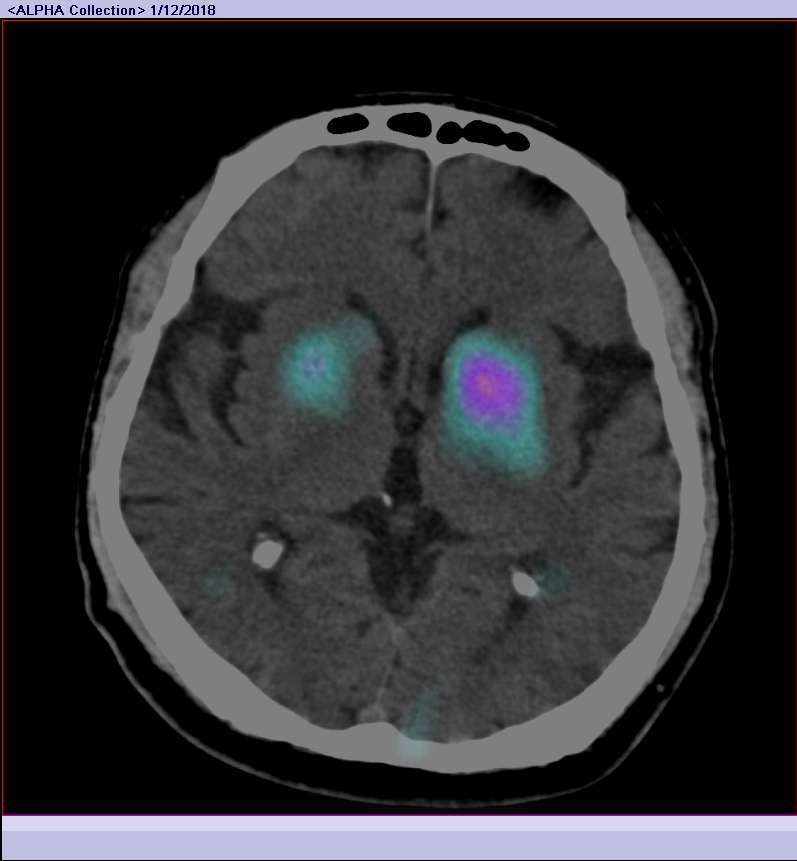

NUCLEAR NEUROLOGY

TRODAT for parkinsonism

SISCOS for epilepsy

ECD/ HMPAO for brain perfusion

Dementia

DAT imaging for Parkinsonsim